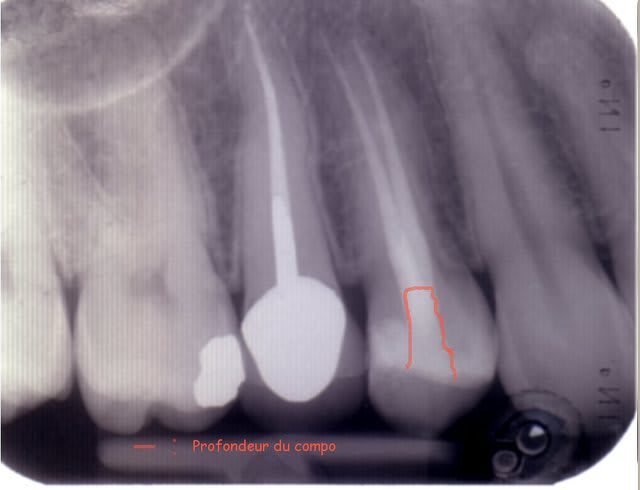

Voila les photos:

1- Préop avec le compo inital infiltré

2-Endo finie

3- 1 semaine apres cavit retiré + compo.

Je vais vous envoyer une nouvelle photo ou je vous montre les limites du compo que j'ai posé aujourd'hui en remplacement du cavit et les douleurs atroces (ndl patiente) qui sont apparues lors du massage avec Ibond préalablement).

Vous remarquerez que ces parois badigeonnées sont strictement supra-osseuses.